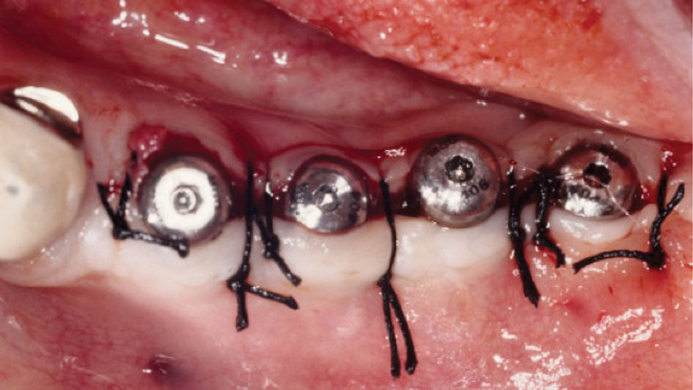

Clinical case: Delayed implant placement: sinus floor elevation by means of lateral

approach & implant placement with GBR

- Courtesy of Dr. Irfan Abas, Netherlands -